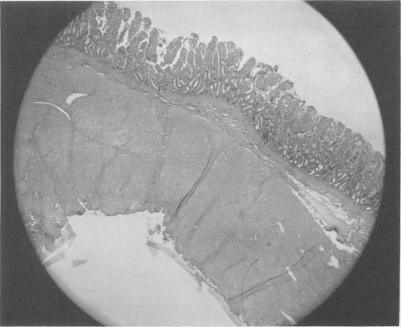

Strangulation obstruction. Closed loop studies.

Ann Surg. 1961 Jan;153(1):94-102. doi: 10.1097/00000658-196115310-00010.

Strangulation obstruction. Closed loop studies.绞窄性梗阻。闭环研究。